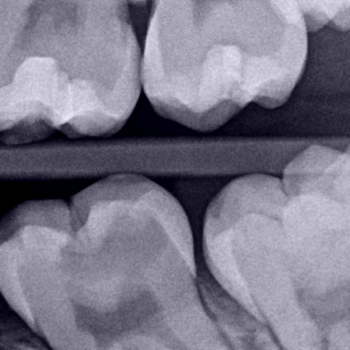

Pacienta s-a prezentat raportând durere de scurtă durată la dintele nr. 19 (Fig. 1). Prin radiografie, o evaluare clinică și o analiză a istoricului clinic al pacientei a fost diagnosticată o leziune carioasă extinsă (Fig. 2) ca și cauză a durerii, ca urmare a unui proces de pulpită reversibilă.

Fig. 2. Radiografia mușcăturii evidențiază o leziune carioasă a dintelui 19. Țesutul submineralizat este găsit în apropierea cornului pulpar mezial.